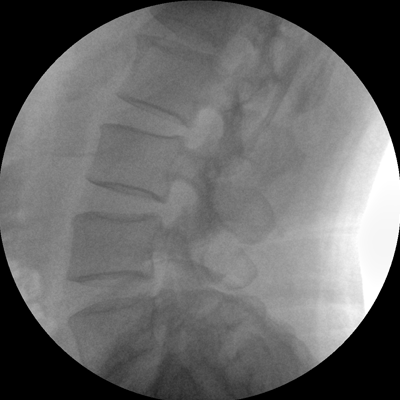

小巧輕便 超凡靈動(dòng) PLX C1116

●全數(shù)字化百萬像素影像系統(tǒng),圖像清晰